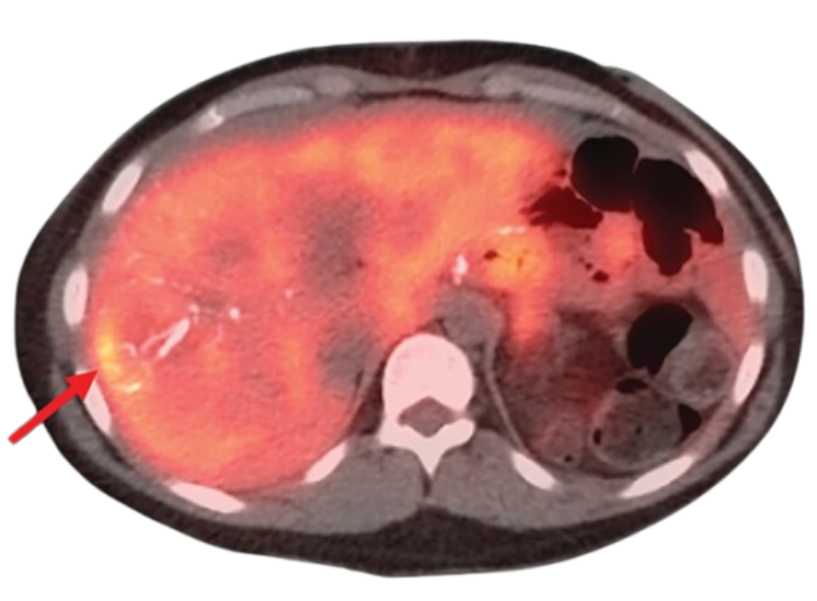

Neuroendocrine tumors (NETs) are a type of cancer that originates in the hormone-producing cells of the body. These tumors can develop in various organs, including the pancreas, lungs, and gastrointestinal tract. Dr. Sasmita Vadgaonkar in Vile Parle specializes in the diagnosis and treatment of NETs, offering a combination of surgical and medical therapies based on the tumor’s location and stage.

Surgical resection is the primary treatment for NETs. Dr. Vadgaonkar works with each patient to determine the best surgical approach, ensuring the removal of the tumor with minimal disruption to surrounding tissues. In some cases, additional treatments such as targeted therapy, chemotherapy, or peptide receptor radionuclide therapy (PRRT) may be used, depending on the type and stage of the NET.